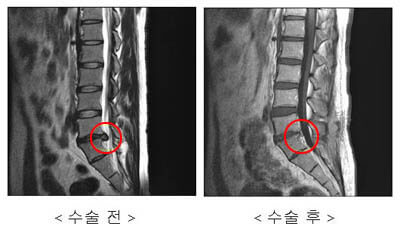

이처럼 퇴행된 디스크와 이미 약해져 있었던 허리 근육은 사소한 충격에도 견디지 못하고 허리디스크를 발생시키게 됩니다. 허리디스크는 척추와 엉덩이 부분을 따라서 다리 쪽으로 가는 좌골 신경을 자극하게 됩니다. 따라서 허리부터 많게는 다리에 까지 통증을 느끼게 될 수가 있다고 합니다. 아래에서 알려 드릴 허리디스크 증상이 발생할 수 있어 의료기관의 도움을 받아 조기 개선을 해줘서야 합니다.